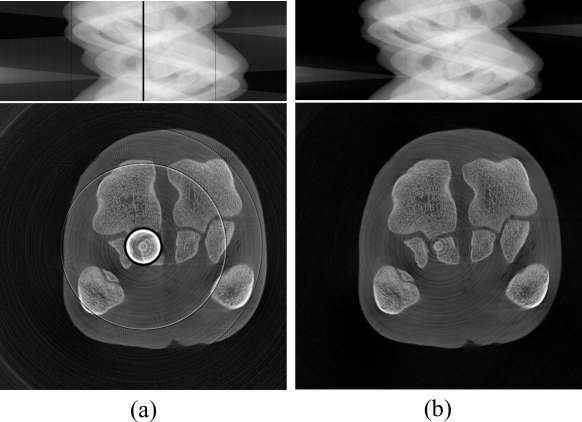

Widely adopted methods for ring artifact removal include detector calibration methods[5, 6, 7], sinogram domain preprocessing methods[8, 9, 10, 11, 12, 13, 14], CT image post-processing methods[15, 16, 17, 18, 19], dual-domain iterative methods [20, 21], and data-driven methods [22, 23, 24, 25]. Detector calibration includes dark-field correction, flat-field correction, and bad-pixel correction. However, equipment aging can lead to deviations in correction coefficients, making it difficult to completely remove ring artifacts by relying solely on detector calibration. To effectively remove these artifacts, detector calibration methods need to be combined with other methods to achieve better correction results. CT image post-processing methods involve Cartesian and polar coordinate transformations, potentially leading to a loss of image resolution. Dual-domain iterative methods leverage features from both the projection domain and the CT image domain to establish optimization functions through iterative solving. However, since the stripe artifacts in the sinogram represent high-frequency information, they manifest not only as ring artifacts in the reconstructed images but also spread throughout the image space, causing additional noise and artifacts. As shown in Fig. 1, (a) shows sinogram data without stripes, and (b) shows sinogram data with a single stripe. (c) and (d) show the FBP[26] reconstructions of (a) and (b), respectively. Comparing Fig. 1 (c) and Fig. 1 (d), besides the ring artifacts, Fig. 1 (d) also shows other noticeable artifacts. Therefore, it is challenging to achieve satisfactory results using single regularization constraints in the image domain. Data-driven supervised learning methods for artifact removal heavily depend on the size and quality of labeled datasets.

Refer to caption

Figure 1: (a) Sinogram data without stripes; (b) Sinogram data with one stripe artifact; (c) and (d) are the FBP-reconstructed CT images from (a) and (b), respectively.